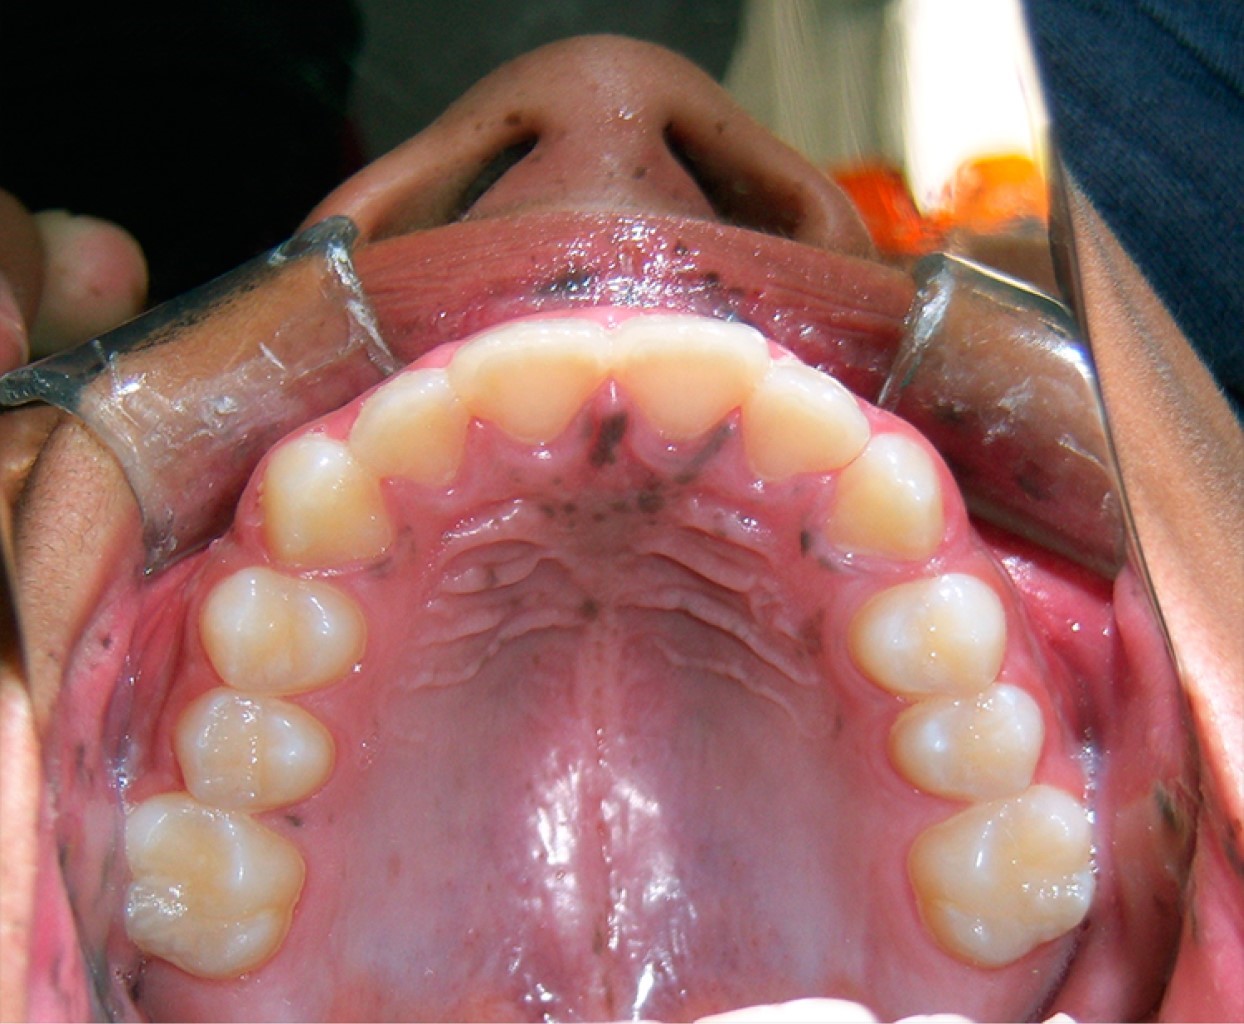

A la exploración clínica se observan múltiples máculas que confluyen entre sí en el borde bermellón del labio superior e inferior, siendo más abundantes en el labio inferior (Figura 1). Presenta también máculas generalizadas en mucosa labial y mucosa yugal (Figura 2), y sólo unas cuantas a nivel de la papila incisiva y paladar duro (Figura 3), respetando la mucosa lingual y piso de boca. El paciente presentó una mancha melánica difusa en la falange distal del dedo índice de la mano derecha (Figura 4).

La zona más frecuente de aparición son los labios y la mucosa de revestimiento (mucosa labial y yugal), pudiendo encontrarse también a lo largo de la mucosa masticatoria (paladar duro y encías). La lengua y la mucosa del piso de boca raramente se ven afectadas.

Las manifestaciones mucocutáneas propias del SPJ, conocidas como melanoplaquias, son un conjunto de máculas hipermelánicas con un diámetro menor de 5 mm cuya coloración puede ser azulada o negruzca, pueden ser únicas o múltiples que confluyen entre sí. Topográficamente aparecen en la piel adyacente a orificios anatómicos como piel peribucal y mucosa bucal, piel periorbitaria, perianal, perigenital y piel de las palmas de las manos y plantas de los pies.4-7

Histológicamente, las máculas bucales presentan acantosis y melanina en la capa basal con melanocitos con procesos dendríticos elongados.7